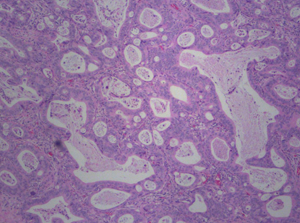

Pleural Fluid with

Metastatic Cancer